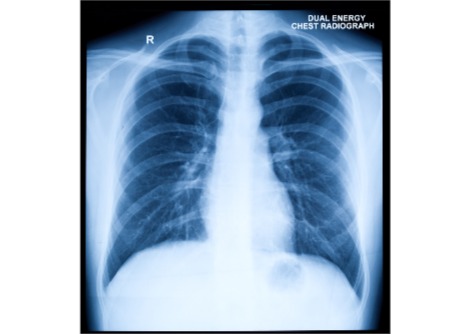

إنّ أكثر من ثلث البالغين في الولايات المتحدة يعانون من السمنة، وتقريباً 30 مليون من الأمريكيين كذلك يعانون من مرض السكّري. إنّ العلاقة كبيرة ما بين الأمرين، فحسب الجمعيّة الأمريكيّة للسكّري فإنّ نسبة %85.2 من مصابي سكّري النوع الثاني يعانون من ازدياد الوزن أو السمنة. في هذه التجربة، يظهر بأنّ كلتا الفئتين من الفئران الأولى ذات الوزن الطبيعي والثانية التي تعاني من السمنة قد أتمّوا 12 أسبوعاً من تمارين الاهتزاز لمدّة 20 دقيقة يوميّاً و 45 دقيقة على آلة المشي الخاصّة بتجارب الفئران والرّاحة.